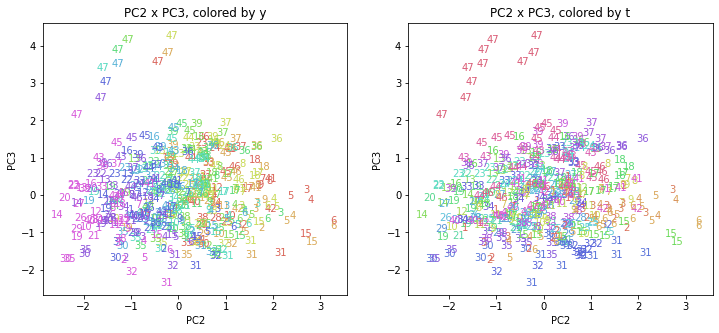

PCAの結果の第n主成分をPCnと表記します。

医療費データの場合と同様に、PCAの結果を見やすく表示するため、seabornのカラーパレットを使って、年月別、都道府県別に色分けして図示してみます(左側が年月別に色分け、右側が都道府県別に色分け)。PC1~PC8まで表示しました。

都道府県番号の表示

上の色分けだけでは都道府県が区別しにくいので、医療費データの場合と同様に、点の代わりに都道府県番号をプロットした図も描いておきます(色分けは上と同じ)。

医療費データの場合ほどはっきりとはしていませんが、PC2が概ね時間の経過を表す成分で、残りの成分が時点によって変わらない地域の特徴を表す成分となっているようです。

また、PC1×PC3を見ると、47沖縄が他の都道府県からかなり離れたところに位置しており、沖縄の地域差が際立っているのが分かります。これは、以前別の記事で年齢階級のない健診データでPCAを実行した場合と似た結果となっています。